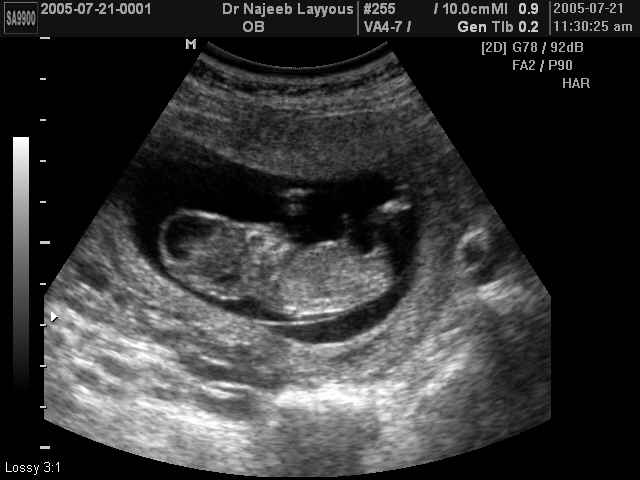

صور طبية للحمل بجهاز الالتراساوند | الدكتور نجيب ليوس